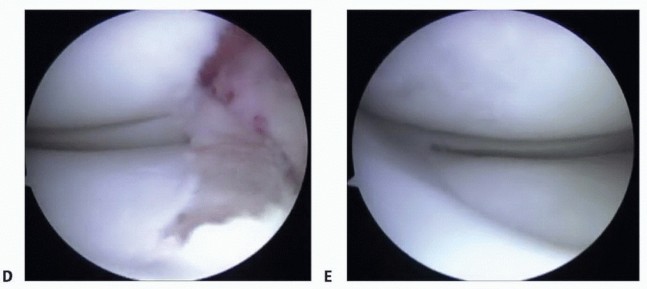

FIG 2

•

A.

AP weight-bearing bilateral knee views showing subtle medial compartment joint space narrowing of the right knee (

arrow

).

B.

MRI showing deficient medial meniscus.

C.

Arthroscopic image of right knee showing deficient medial meniscus.

A detailed history includes specific symptoms, prior injuries, and subsequent surgery. Arthroscopy pictures are helpful in determining the degree of meniscal resection and the condition of the articular cartilage.

Anteroposterior (AP) view of both knees in full extension (

FIG 2A

): Look for subtle joint space narrowing.

Magnetic resonance imaging (MRI): to assess menisci, articular cartilage, and subchondral bone (

FIG 2B

)

Diagnostic arthroscopy is often recommended.

It will accurately define the extent of meniscectomy and the degree of arthrosis if previous arthroscopic images are unavailable or unclear or if more than 6 months to 1 year has elapsed since the last arthroscopy (

FIG 2C

Outerbridge grade III or less articular cartilage damage is acceptable (grade I or II is preferable). A focal grade IV lesion may be addressed concurrently with a cartilage resurfacing procedure. Diagnostic arthroscopy may also assist in planning the optimal method for addressing the articular cartilage lesion.